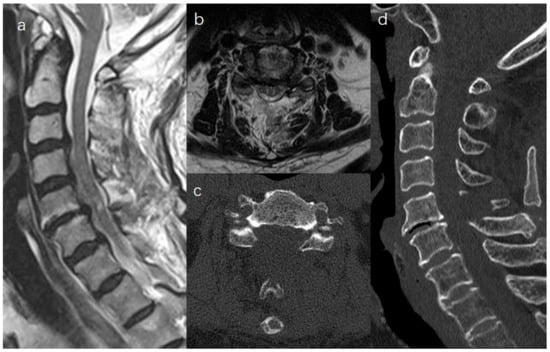

:1. Introduction

2.2. Surgical Procedure

2.2.2. Unilateral Biportal Approach for Bilateral Laminectomy (Video S1)